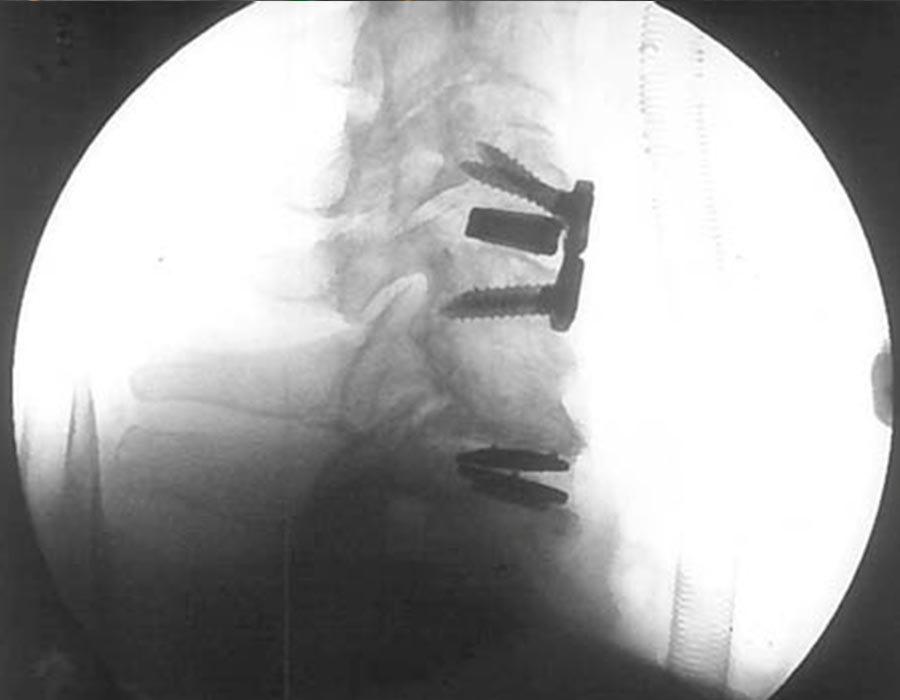

cirugia avanzada de columna cervical

• Discectomía anterior C4-C5 y artrodesis intersomática con PEEK titanio e injerto autólogo y placa ABC , añadiendose Cobertura dural con Lyoplant

• Discectomía anterior C6-C7. Foraminotomía bilateral/barras osteofitarias y artroplastia C6-C7 Activ C

• Se objetiva control radiológico satisfactorio.